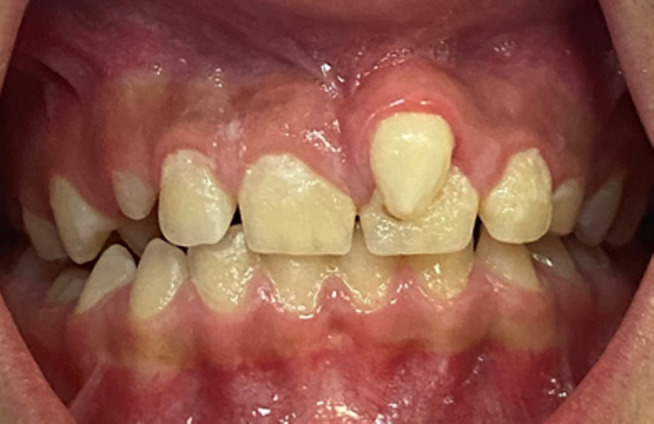

• 口內照片顯示上頜左中切牙唇面有一顆錐形多生牙

• 額外切牙可以出現(xiàn)在上頜中線或偏側位置,并且通常表現(xiàn)為小于正常牙齒或形態(tài)不規(guī)則。